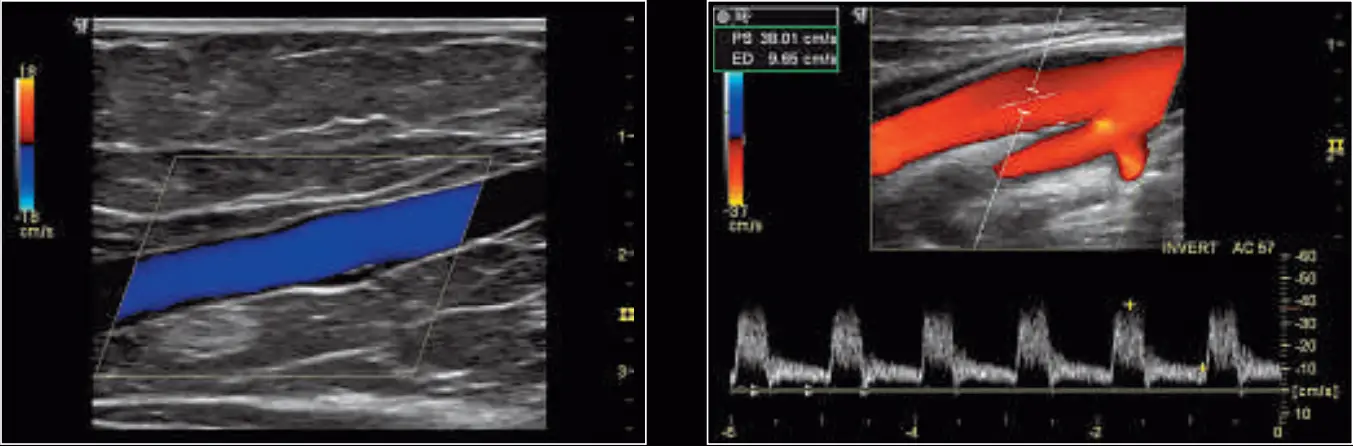

| Renal artery and vein displayed using the 11L probe and a combination of virtual convex, fundamental imaging, and SRI | High-frequency scan of parathyroid and irregular thyroid tissue; Phase Inversion Harmonics and SRI used to show maximum homogeneity and detail resolution |

| 11L sagittal vein with color Doppler using the 11L probe with Phase Inversion Harmonics, CrossXBeam, and SRI features | An internal carotid artery with color and pulse wave Doppler using the 11L probe with Coded Harmonics, CrossXBeam and SRI |